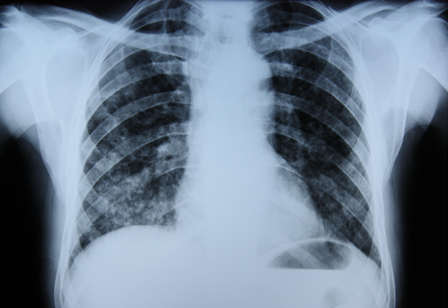

A doença afeta tipicamente pacientes com asma ou fibrose cística, mas também está associada à baixa imunidade. Sorologia para Aspergillus pode ajudar a dar suporte ao diagnóstico. A sensibilidade ao organismo no teste cutâneo de puntura também é um útil adjuvante ao diagnóstico.[Figure caption and citation for the preceding image starts]: Radiografia torácica de um paciente com pneumonia eosinofílicaDo acervo de Athanasia Pataka, MD [Citation ends].